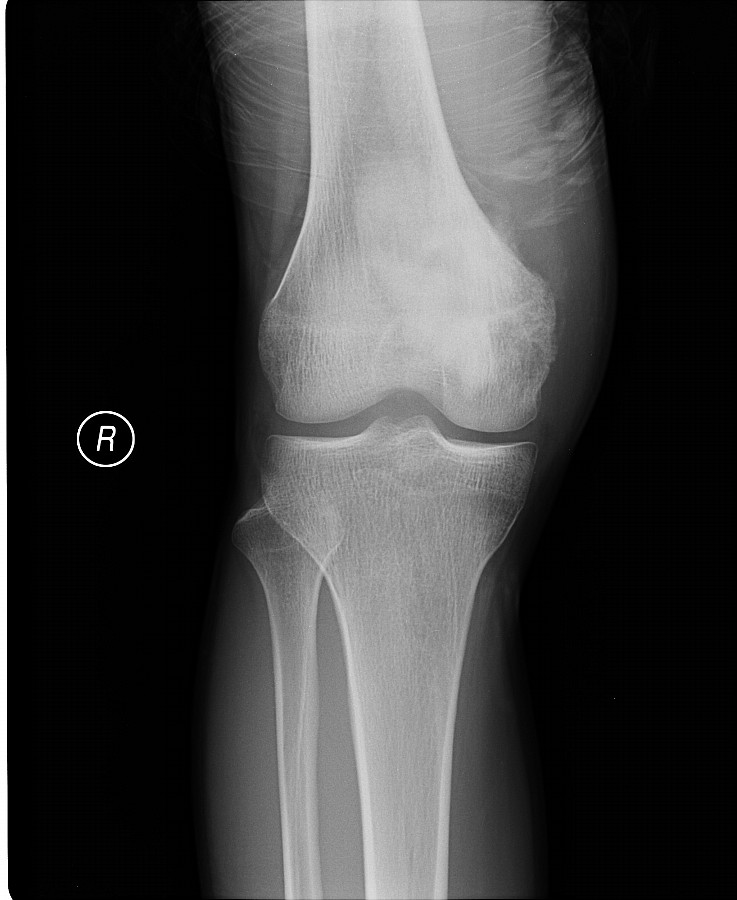

以下是引用黑白光影在2009-3-13 13:00:00的发言:[br]考虑右股骨远端内侧缘絮样骨质密度影,髁上可见骨膜反应,相应侧软组织肿胀,考虑成骨肉瘤可能。

以下是引用guo430726在2009-3-13 13:50:00的发言:[br]考虑右股骨远端内侧缘絮样骨质密度影,髁上可见骨膜反应,相应侧软组织肿胀,考虑成骨肉瘤可能。[br]支持!